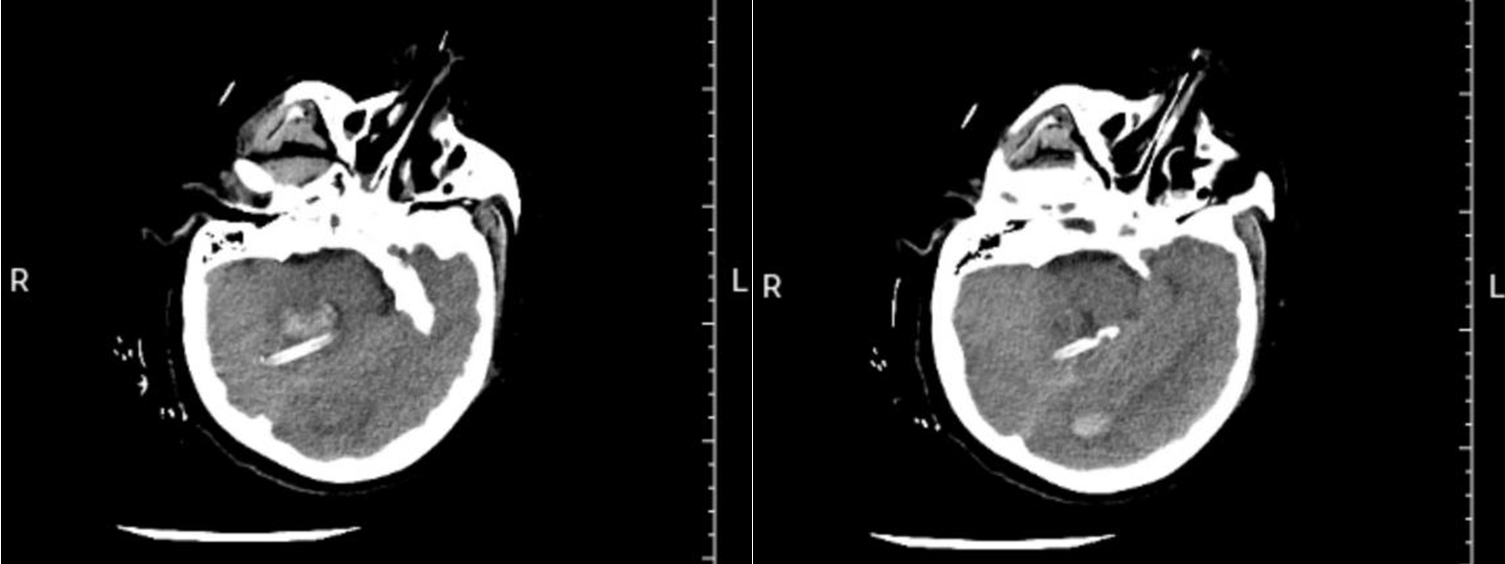

上图所示为患者术后当日复查颅脑CT。

患者收治到急诊重症监护病房后,东院神经外科刘建辉主任医师、胡佳主任医师、薛昆副主任医师、吕新亭主治医师,急诊重症监护病房潘继明主任医师对患者的病情进行了全面评估,认为患者颅后窝出血量大,压迫脑干,已出现意识障碍,昏迷,血压、心率不稳等表现,随时都有心跳停止的可能,手术指征明确,但患者生命体征不稳,手术风险极大,无法耐受开颅手术。经过综合考虑,决定为患者实施微创脑内血肿穿刺引流术,征得患者家属同意后,立即开通“绿色通道”,快速完成术前准备,紧急将患者送至手术室。麻醉科尚书军主任医师评估病情后为其进行了全身麻醉并更换喉罩为气管插管。手术医师首先在患者右侧额部发迹内头皮切开约3mm的切口,快速进行侧脑室穿刺手术,释放血性脑脊液,解除了患者脑积水病情,为后续小脑出血手术争取时间,然后调整体位,根据术前影像检查进行血肿穿刺规划,沿穿刺点精准置入引流管1根,术中抽出血肿15ml,手术快速顺利完成。术后在急诊重症监护病房及神经外科医护人员的精心呵护下,患者逐渐恢复意识,术后3周完全恢复正常,顺利出院。